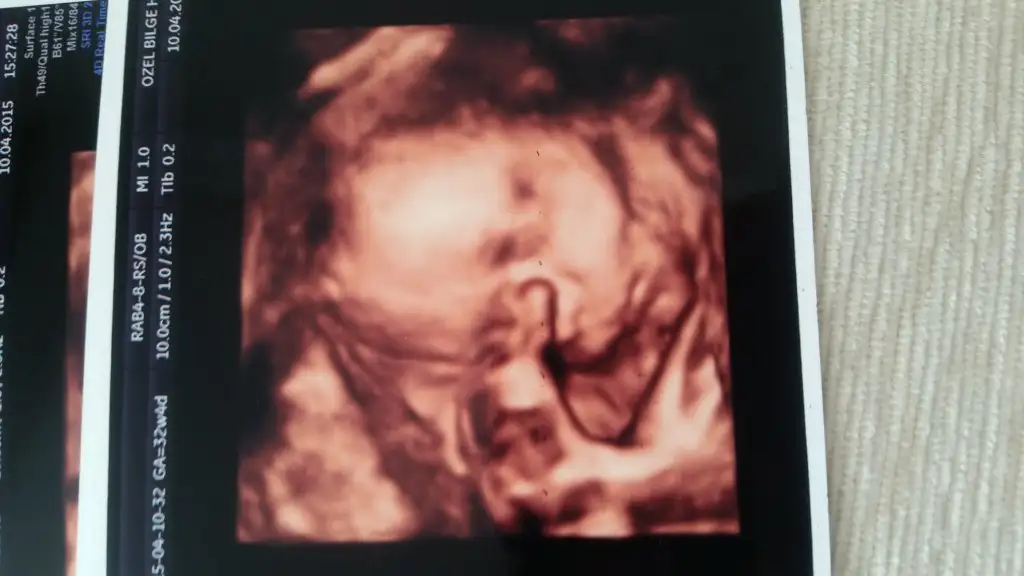

Maşallah yerimm seni bennn oyş kurban olduklarım32+4 de biiizzz:)